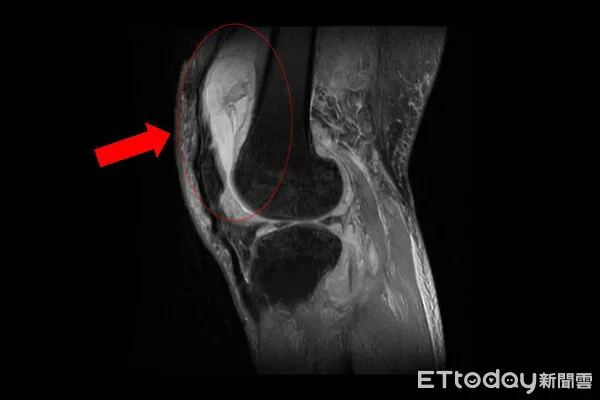

▲一名患者膝關節疼痛,竟是「肺外結核感染」。(圖/院方提供,下同)

台中慈濟醫院關節中心主任周立展指出,該患者長期左膝腫痛、幾乎無法行走,以為只是退化性關節炎,服用止痛藥、抽關節積水、熱敷復健,但卻越來越嚴重,就醫時膝蓋已腫脹無法彎曲,化驗後發現白血球數值雖偏高,但並非典型的細菌感染,懷疑有其他原因,進一步X光與磁振造影檢查,顯示膝蓋內已有大量積液並化膿,屬於嚴重關節感染。

周立展說,緊急施行微創關節鏡清創手術,檢體送病理化驗後竟發現結核分枝桿菌,顯示並非單純膝蓋退化,會診感染科與胸腔科醫師共同診斷,在病人痰液培養出結核菌,證實為「肺結核合併肺外感染」,結核菌最初在肺部引起感染,再經由血液或淋巴傳播,最後侵犯膝關節。